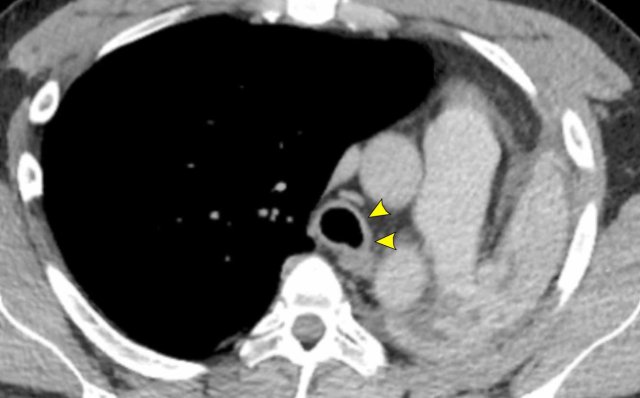

Image

Tracheobronchial

papillomatosis with lung involvement in a 54 y.o male, showing two papillomas

in the trachea.

Continue with the lung window...

The image shows multiple cystic lesions in both lungs (arrowheads).

In rare cases extension into the lung parenchyma can occur, showing cystic nodules most often in the dependent apical segments of the lower lobes. There is a small risk of malignant transformation from squamous cell papilloma into squamous cell carcinoma.